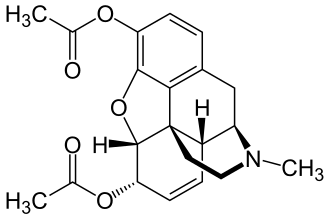

Heroin ist durch zwei Acetylgruppen lipophiler als Morphin, weshalb es wesentlich leichter die Blut-Hirn-Schranke passieren kann.

Heroin ist durch zwei Acetylgruppen lipophiler als Morphin, weshalb es wesentlich leichter die Blut-Hirn-Schranke passieren kann.

Das Diffusionsvermögen eines Moleküls durch die Endothelien der Blut-Hirn-Schranke wird vor allem durch seine Fettlöslichkeit (Lipophilie) und Größe bestimmt. Durch eine Modifizierung des Moleküls mit lipophilen Gruppen kann deshalb eine verbesserte Gehirngängigkeit erreicht werden.[33] Ein klassisches Beispiel hierfür ist die Di-Acetylierung des Naturstoffes Morphin zu Diacetylmorphin (Heroin). Heroin (log P=1,12) zeigt gegenüber Morphin (log P=0,2) eine über 25fach höhere Aufnahme im Gehirn (siehe dazu: Tabelle 1).[34] Entsprechende Ergebnisse werden beim Brain-Uptake-Index (BUI) für radioaktiv markiertes Morphin, Codein und Heroin erhalten, das in die Halsschlagader injiziert wird. Für Morphin liegt der BUI unterhalb der Nachweisgrenze, bei Codein bei 24 % und für Heroin bei 68 %.[35]